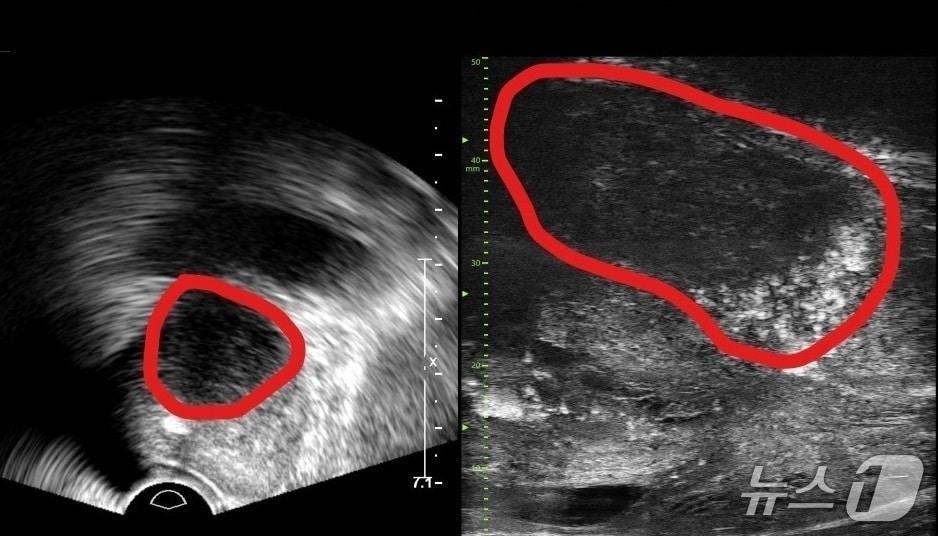

본문 이미지 - 기존 전립선 초음파 사진(왼쪽) 및 마이크로 초음파 사진(오른쪽). 기존 초음파는 전립선 부위(동그라미 친 부분)의 음영 차이로만 병변을 확인했지만, 마이크로 초음파는 높은 해상도를 통해 종양과 주변 조직의 모양까지 확인할 수 있다.(분당서울대병원 제공)

기존 전립선 초음파 사진(왼쪽) 및 마이크로 초음파 사진(오른쪽). 기존 초음파는 전립선 부위(동그라미 친 부분)의 음영 차이로만 병변을 확인했지만, 마이크로 초음파는 높은 해상도를 통해 종양과 주변 조직의 모양까지 확인할 수 있다.(분당서울대병원 제공)